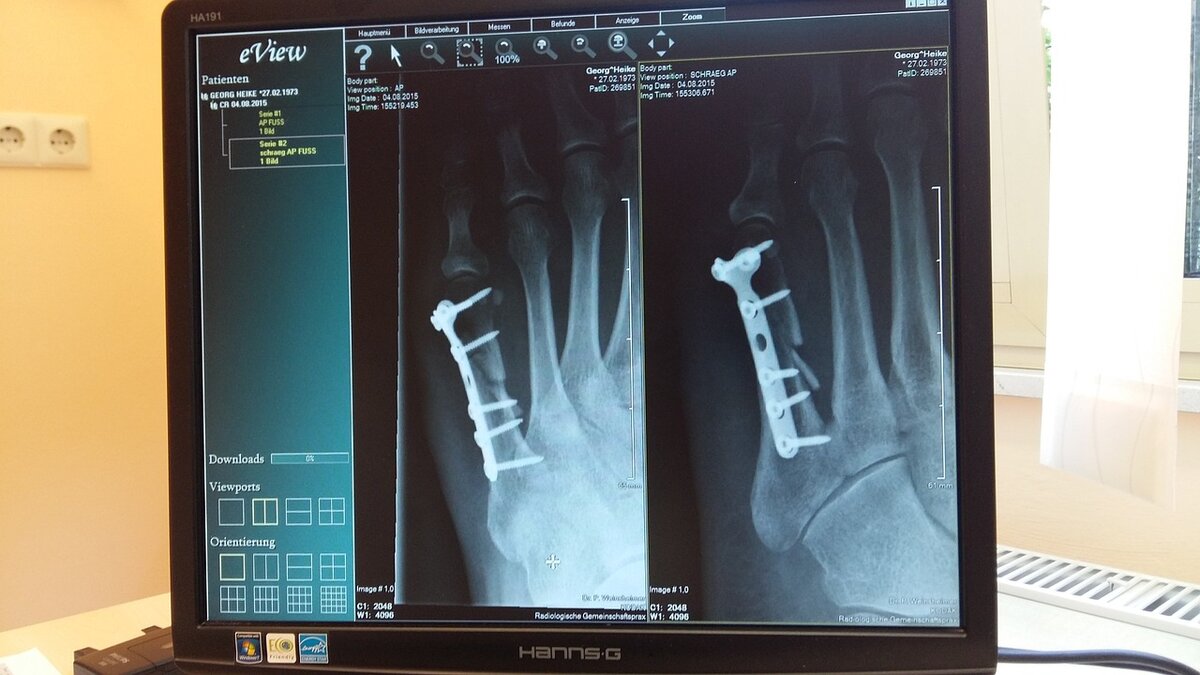

Рентгеновские лучи ценны в медицине, потому что они могут видеть сквозь определенные части тела.

Врачи могут делать снимки костей, зубов и тканей. Они используют эти фотографии, чтобы увидеть, какие кости сломаны или выяснить, какие зубы имеют отверстия в них.

Для получения рентгеновских снимков нужны две вещи: специальная пластина, которая может захватывать рентгеновские лучи, помещается позади части тела человека. Перед человеком ставят аппарат, который производит рентгеновские лучи.

Рентгеновские лучи достаточно сильны, чтобы пройти через кожу и мышцы, но они не могут пройти через твердые предметы, такие как кости.

На картинке вы видите твердые предметы, такие как кости, как белые участки. Объекты, через которые проходят рентгеновские лучи, темны.